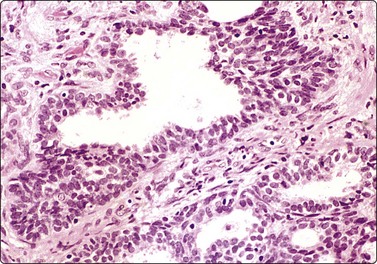

Tumors of more than one histologic type (mixed forms) (Figs 13.35 and 13.36)14,60,63,65

While the basic GCT types are infrequent in pure forms they are very frequent in mixed forms. Embryonal carcinoma and teratoma are each present in 47% of cases, and yolk sac tumors in 41%; 40% of TGCT contain varying numbers of syncytiotrophoblastic cells.12

image

Fig. 13.35 Tumor of more than one histological type (mixed form)

Large bisected tumor occupying most of the enlarged testicle in a male 19 years of age. Note hyalinized, degenerate and cystic areas.

image image

Fig. 13.36 Tumor of more than one histological type (mixed form)

(A) Well-differentiated glandular epithelium (right), large malignant cells similar to embryonal carcinoma (left) (MGG, HP); (B) Corresponding tissue section (A, H&E, IP; B, PAP, IP).

Criteria for diagnosis

Cellular aspirates; necrosis and hemorrhage frequent,

Three-dimensional clusters of epithelial malignant cells as described above

Coexisting teratomatous structures represented by mature or immature tissues originating from one or more blastodermal leaf: fusiform naked nuclei embedded in a myxoid background resembling embryonal mesenchyme; islets of cartilage; sheets of epithelial cells, which may be squamous, ciliated or intestinal (with goblet cells); bundles of fusiform cells with blunt ends reminiscent of leiomyoma; tight clusters of deeply stained bare nuclei may correspond to primitive neuroectodermal tissue.

The diagnosis of mixed forms is simple when malignant elements of an epithelial nature coexist with clear-cut teratomatous structures. Necrosis may obscure the neoplastic cells and the teratomatous component may be only minor or even absent. This can be explained by its greater cohesion causing under-representation in FNA samples. As a result, the differential diagnosis between mixed TGCT and embryonal carcinoma is sometimes difficult or impossible.14,59-61,65,66 The presence of multinucleated syncytial cells is not diagnostic of choriocarcinoma.